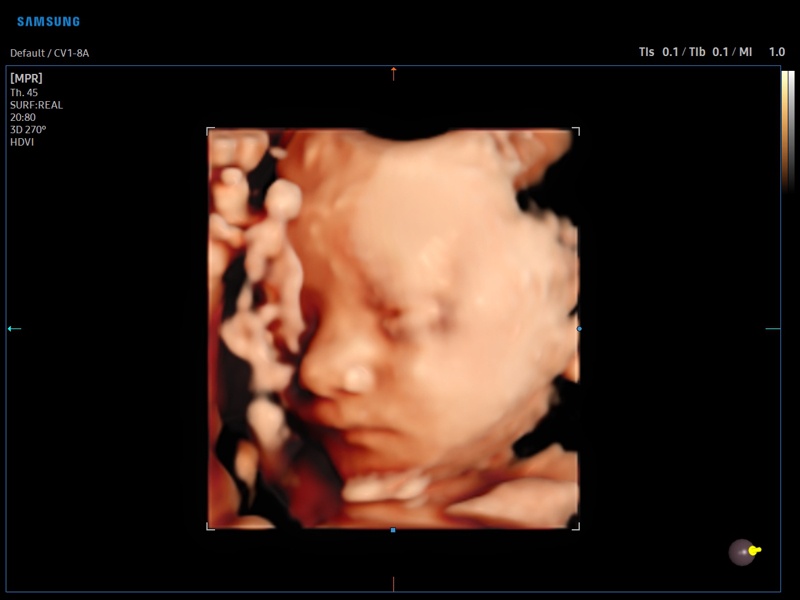

Fetal face, RealisticVue, 3D

Fetal face, RealisticVue, 3D (echogramm №884)

[RU] Ultrasound image №884: Fetal face in RealisticVue™ mode (3D probe 1-8 MHz).

Echogramm was received by ultrasound scanner V8 (available for sale).